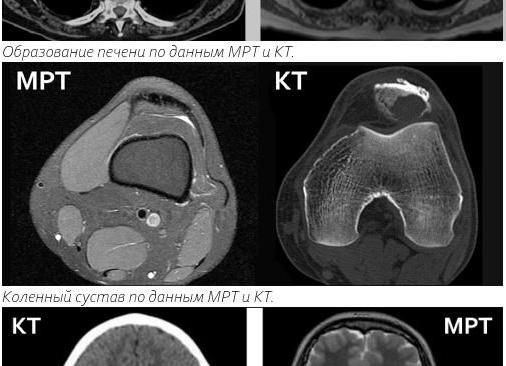

Иногда врач назначает не МРТ, а КТ печени. В чем разница? МРТ основана на определении электромагнитного отклика атомных ядер при нахождении в магнитном поле сильной напряженности. А компьютерная томография (аббревиатура КТ) – на измерении разности рентгеновского излучения, проходящего через ткани разной плотности. Оба эти метода послойно сканируют органы и выдают на экран снимки высокого разрешения. Эти способы не инвазивны и безболезненны. Доза рентгеновского облучения при КТ печени минимальна по сравнению с простым рентгеновским снимком. При одноразовом сканировании оба метода безопасны. Однако частое и длительное проведение КТ увеличивает дозу облучения, что может вызвать нежелательную реакцию организма.